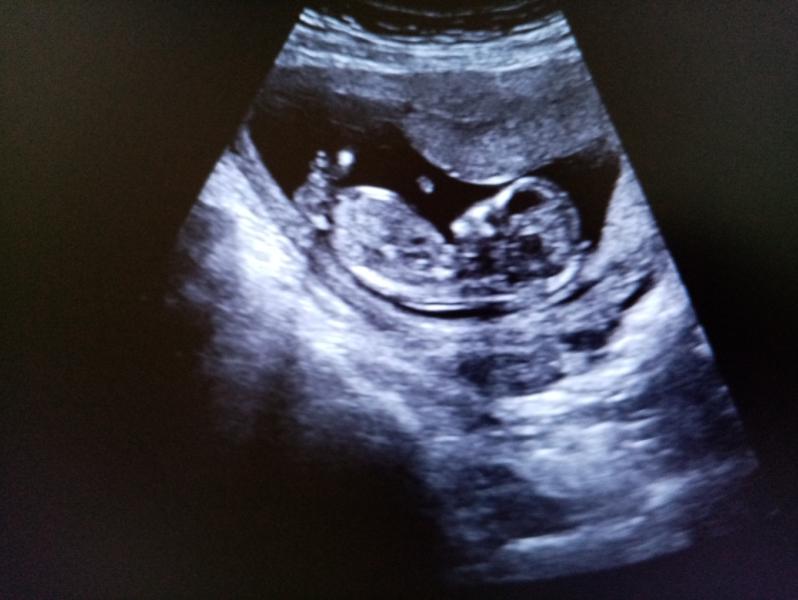

На УЗИ нам 12 недель 😇 А на фото с пузиком 20 недель 🥰